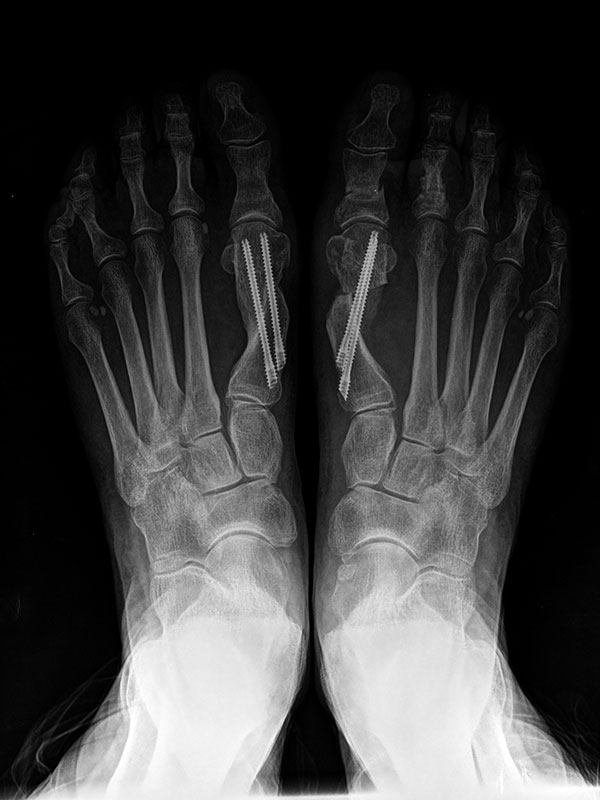

En el hallux valgus y en las fases incipientes del hallux rigidus fijamos la corrección deseada con tornillos (cirugía percutánea de 3ª generación) lo que confiere más estabilidad y por tanto nos permite conseguir unas mayores correcciones de la deformidad sin apenas dolor respecto a otras técnicas percutáneas.

Después